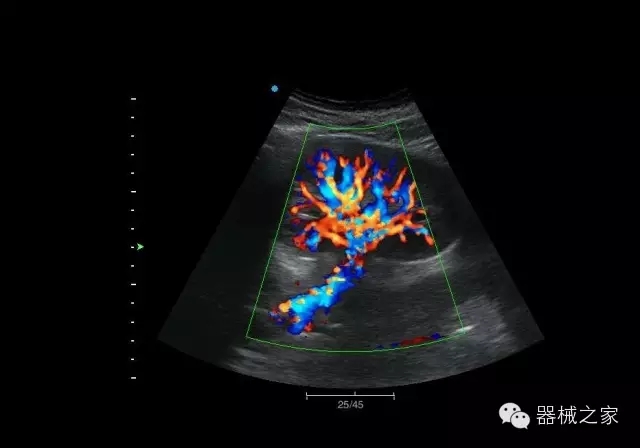

臍帶血流